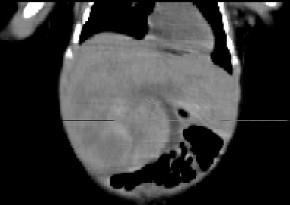

男,5天,上腹部膨隆,CT所见如图,最可能的诊断是 ( )A、肝脓肿B、肝转移瘤C、肝母细胞瘤D、肝血管瘤E、原发性肝癌

问题 男,5天,上腹部膨隆,CT所见如图,最可能的诊断是 ( )

选项 A、肝脓肿 B、肝转移瘤 C、肝母细胞瘤 D、肝血管瘤 E、原发性肝癌

答案 C